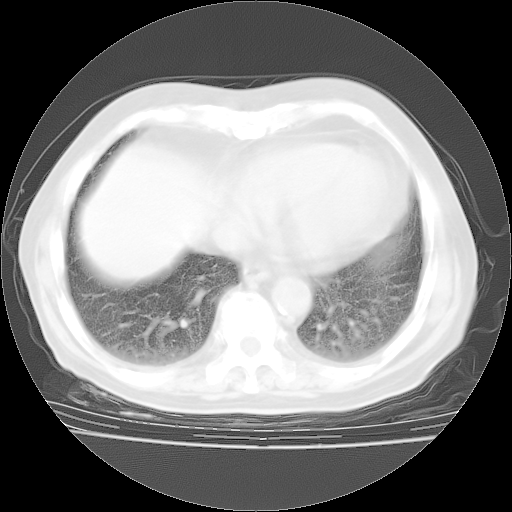

轻微咳嗽,无痰,(体温正常时)R20次/分,P75次/分,双肺底、腋下可闻及少量捻发音。下肢轻度浮肿。

增加治疗:异烟肼、利福平、乙胺丁醇,静滴左氧氟沙星、参麦注射液。甲强龙从80mg暂减为40mg。